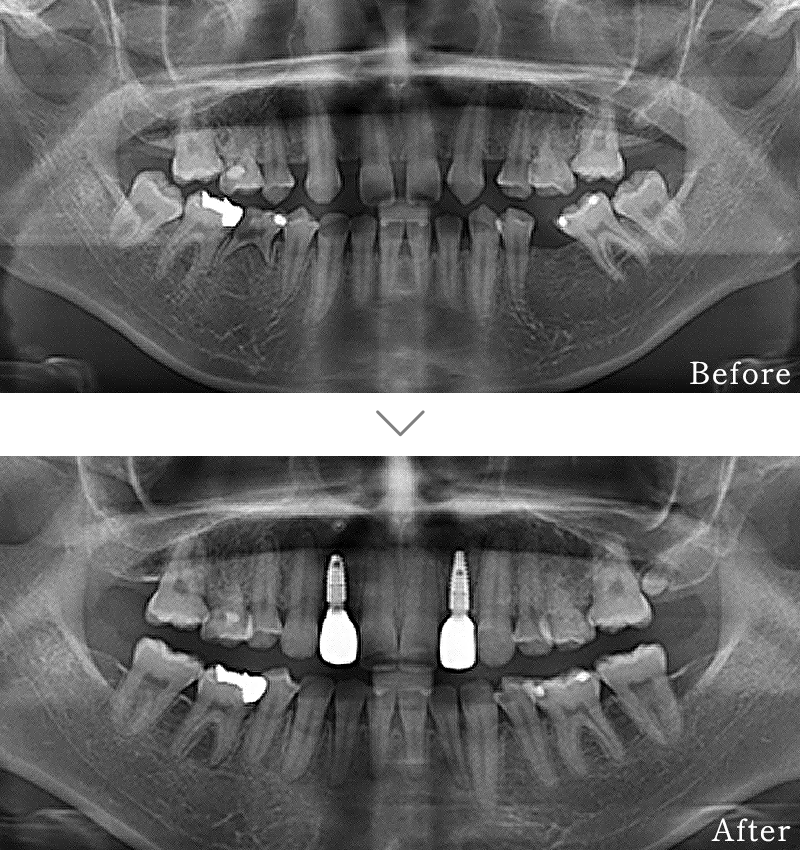

CASE2

主訴 奥歯でしっかりと噛むことができない、入れ歯もすぐに壊れてしまうとのことで来院されました。

治療法 下の奥歯を右1本、左2本のインプラントとセラミックの被せ物で噛み合わせを回復しています。

治療期間 4ヶ月

費用 CT:16,500円(税込)

+ インプラント治療:1,577,400円(税込)

合計:1,593,900円(税込)

副作用

• 歯周病に感染・発症し重度に進行するとインプラントが抜けてしまうことがあります。

• 手術後は数日間腫れが出る場合があります。